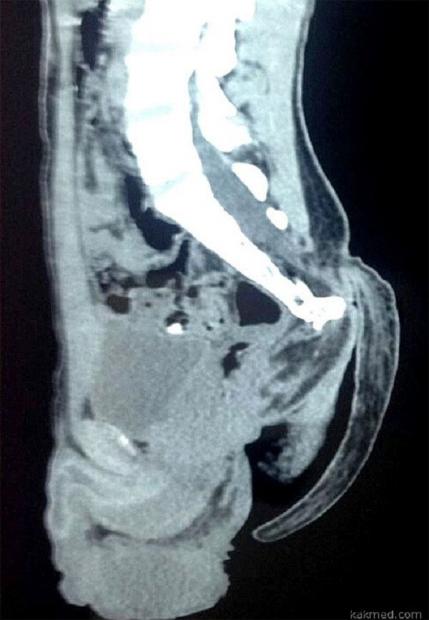

Hình ảnh chụp phim x-quang của bệnh nhân thể hiện rõ chiếc đuôi dài.

Đuôi dài 17,78cm của nam thanh niên 18 tuổi người Ấn Độ.